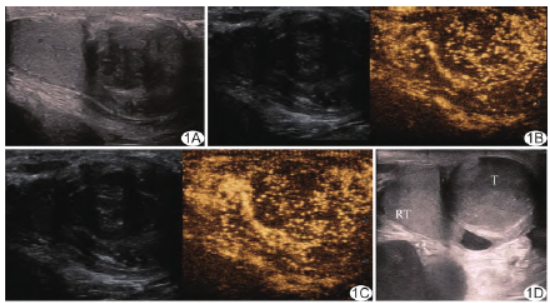

患者男,64岁,阴囊右侧坠胀不适3月余;既往无特殊病史。查体:阴囊右侧肿大,无触痛,表面皮肤无明显异常。超声:右侧睾丸中下极25mm×35mm实性低回声结节,内部回声不均,边界不清(图1A),CDFI于其周边及内部见点状血流信号,阻力指数(resistance index,RI)呈低阻型;超声造影呈“快进快退”等增强模式(图1B、1C);右侧睾丸向右移位约2cm,另于其左外侧见29mm×37mm实性较均匀低回声结节,边界清晰(图1D),CDFI于其周边及内部见点条状血流信号,RI呈低阻型;造影呈“快进慢退”高增强模式(图1E、1F);弹性成像示2个结节硬度均高于正常睾丸实质;提示阴囊内多发恶性结节(肉瘤?)。

图1 睾丸旁混合型脂肪肉瘤 A~C.右侧睾丸中下极肿物(A)于30s灌注达峰(B)、40s廓清(C);D~F.右侧睾丸左外侧肿物(D)于28s达峰(E)后缓慢消退(F) (RT:右侧睾丸;T:肿物)